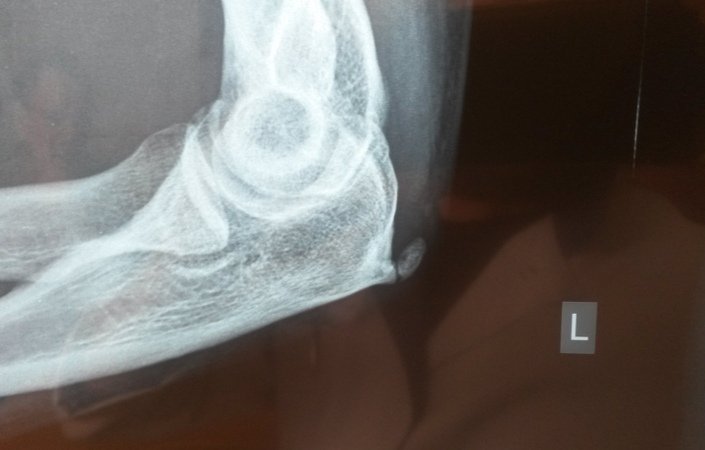

Диагностические мероприятия

Сначала врач проводит беседу для сбора анамнеза, затем выполняет визуальный осмотр и общий анализ состояния пациента. После этого назначаются следующие исследования:

- рентгенография;

Эти методы диагностики позволяют оценить состояние костной ткани и суставов, а также выявить уровень проводимости и степень поражения нервных волокон. Анализ крови помогает обнаружить возможные инфекционные процессы в организме. Сбор полной клинической информации позволяет точно установить причину появления остеофитов и назначить соответствующее лечение.